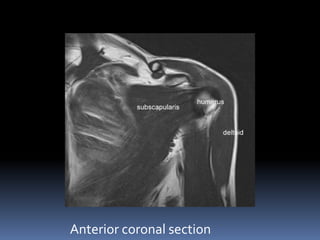

Anterior coronal section